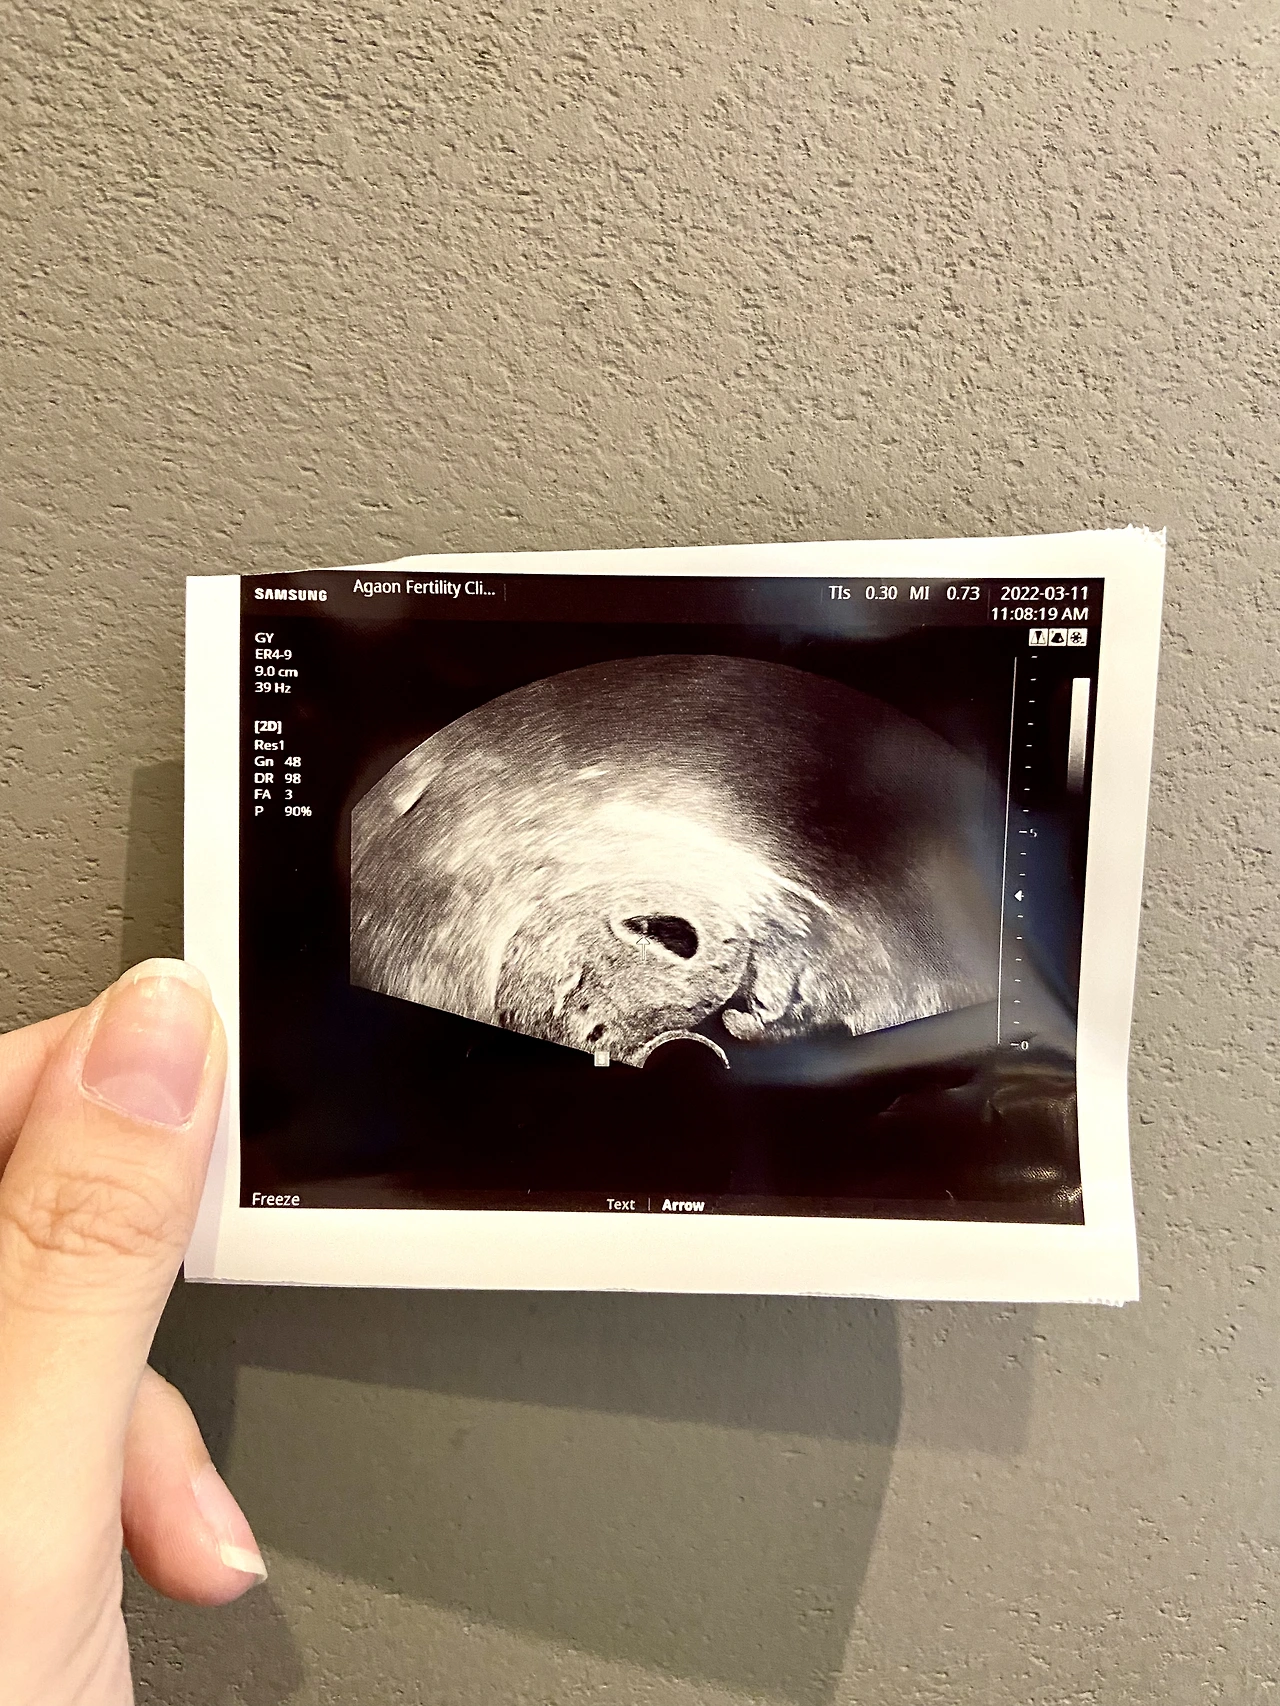

3월 4일 (남편 생일날) 첫 초음파!!! 드디어 자그마한 아기집을 발견 +_+ (4주 차로 추정, 병원에서 소견서 받음)

3월 11일 좀 더 커진 아기집 확인, 아직 아기의 형체까지는 보이지 않았음 (5주 차, 양가 부모님께는 이때 말씀드림, 우리 엄마한테 이야기할 때는 아무렇지도 않았는데 왜 시엄니 목소리 들을 땐 울컥했는지 T_T 스벅에 앉아있다가 눈물 찔끔..)